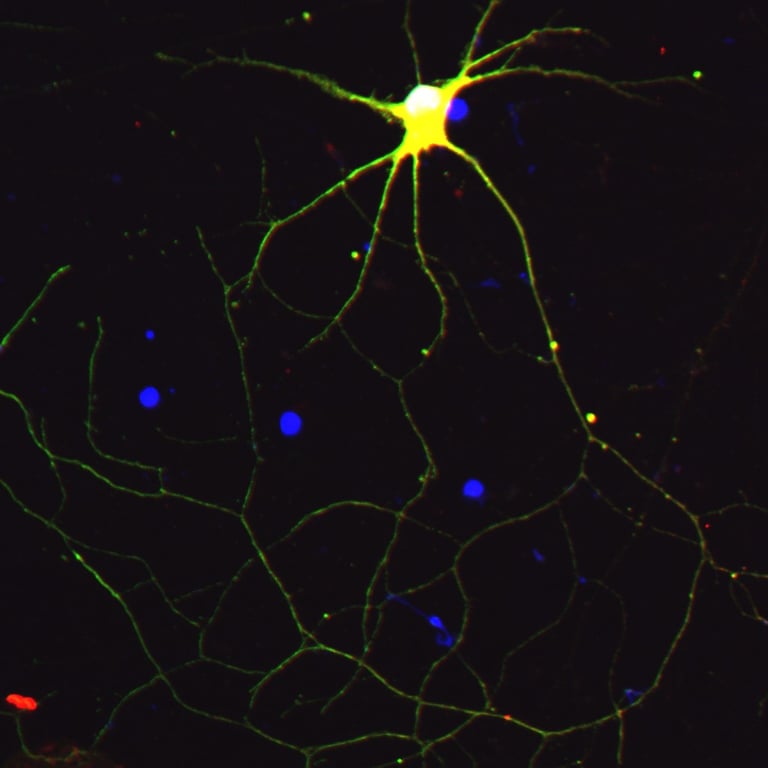

iPSC-derived Neurons